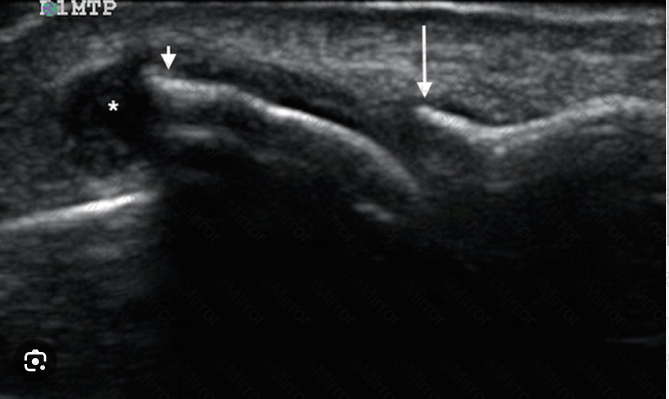

The orthogonal images of a supraspinatus tendon shown here are MOST consistent with which of the following?